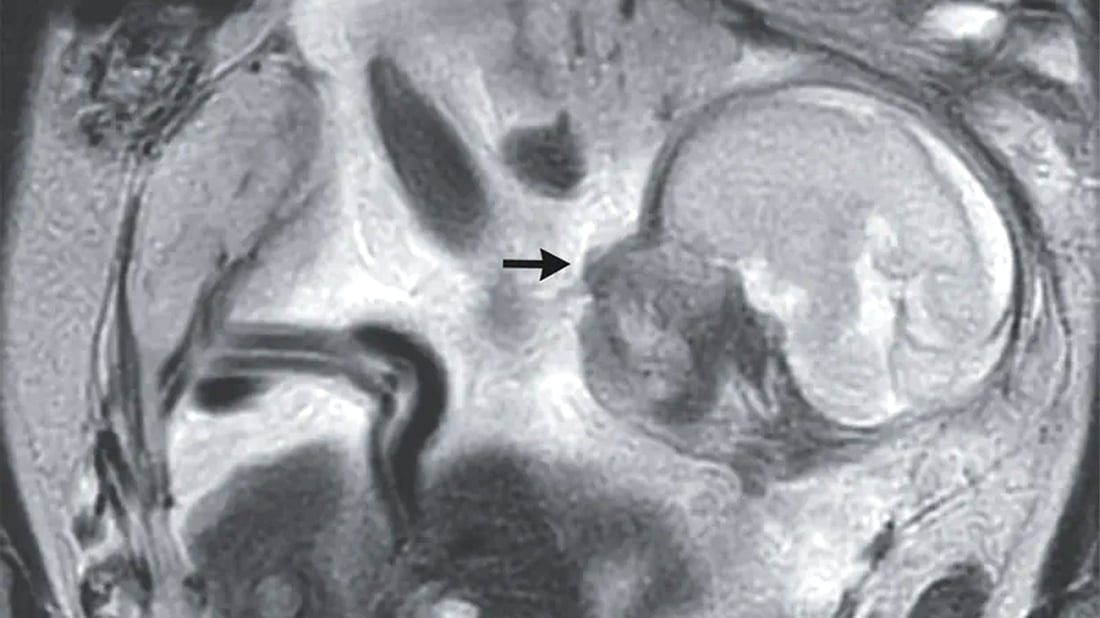

لە بەریتانیا خانمێکی تەمەن 37 ساڵان، دوای ئەوەی تووشی گرژبوون و ئاواسانی گەدە بووە، سەردانی پزیشکی کردووە، دواتر بۆی دەرکەوتووە 23 هەفتەیە منداڵێکی ساوای هەیە، بەڵام کێشەکە لەوە بووە، منداڵەکە لە دەرەوەی منداڵداندا دروست بووە.

پێشتر دووجار بە شێوەیەکی سروشتی دووگیان بووە و پشکنینەکانی دەریانخستووە کە ئەم کۆرپەلەیەش “ئاسایی دەردەکەوێت” و لە گەدەیدا گەشە دەکات.

کاتێک دووگیانییەکەی 29 هەفتەی تەواو بوو، ژنەکە نەشتەرگەرییەکی بۆ کرا و پزیشکەکان سکیان بڕی و منداڵەکەی لەدایکبوو، بەڵام گواسترایەوە بۆ بەشی چاودێریی چڕی تازەلەدایکبووان.